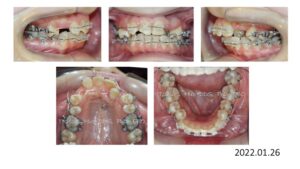

8歳の時、I市の歯科医院で、顎が狭くて歯が入りきらない、顎を拡げなければいけないといわれ、治療を開始したそうですが、6年経っても治療が終わらないどころか、写真のように全く噛み合っていないために、14歳の時にセカンドオピニオンで ひろ矯正歯科に来られました。

臼歯関係は、右が 4㎜ II級。左が 7㎜ II級で、7番しか咬合しておらず、著しい開咬を呈していました。

これは、拡大を始める前の写真ですが、口腔内写真を見る限り、拡大する必要はないです。

8歳からリンガルアーチで拡大を開始し、3年間拡大を続け、12歳でマルチブラケットを付けて治療を開始したそうですが、開咬が治らないためにアンカースクリューを4本打って治療を続けたとのことです。

こんなスクリューじゃあ何の意味もありません。

まさにやっている事がデタラメです。

ひろ矯正歯科に来られた時には、口腔内清掃状態は悪く、全ての歯が齲蝕でボロボロ、要治療でした。

治療中はブラッシング指導は一切無かったそうです。

検査、診断の結果、この患者さんは矯正のみで治療することは不可能、上下顎骨の離断が必要で外科矯正となりました。

この患者さんも歯が入らないから、顎を拡げましょうと言われ拡大を続けましたが、治療前の状態をみると、判断を誤っていることがわかります。